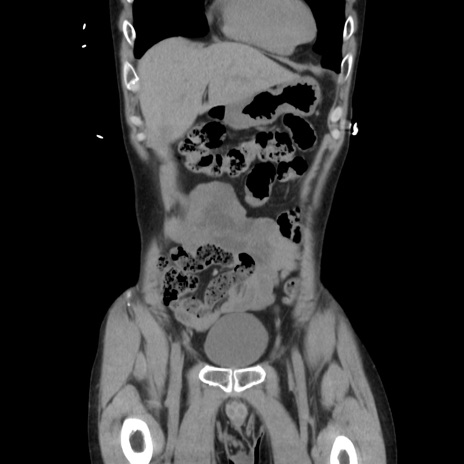

横断像

【症例】40歳代 男性

【主訴】腹痛

【現病歴】4時間ほど前に電車に乗車中に臍部上より腹痛出現。徐々に増悪し起立困難となり、救急外来受診。生ものは数日食べていない。今朝お雑煮を食べた。

【身体所見】BT 36.8℃、BP 117/84mmHg、HR 91/min、SpO2 97%、苦悶様、腹部:臍上部広範囲圧痛あり、反跳痛±

【データ】WBC 8100、CRP 0.03